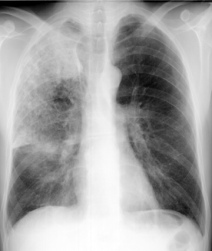

Sogar Feten [Föten] und Säuglinge sind in Leber und Nieren

bzw. in Gehirn und Nieren als Folge von Amalgamfüllungen

der Mutter bereits quecksilberbelastet (Drasch et al.

1994). Das Ausmass dieser fetalen bzw. frühkindlichen

amalgambedingten Quecksilberbelastung ist gravierend:

Babys (im Alter von 11 - 50 Wochen) von Müttern mit mehr

als 10 Amalgamfüllungen wiesen - in Korrelation mit dem

Amalgamstatus der Mütter - Werte von bis zu

2.543,8 µg Hg / kg

Nierengewebe

(Feuchtgewicht, so auch bei den folgenden Gewichtsangaben)

auf. Diese amalgambedingte Quecksilber-Konzentration liegt